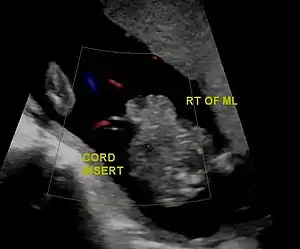

| Gastrochisis in ultrasound: defect is right to midline | |

There are no signs during pregnancy. About sixty percent of infants with gastroschisis are born prematurely.[5] At birth, the baby will have a relatively small (<4 cm) hole in the abdominal wall, usually just to the right of the belly button.[6] Some of the intestines are usually outside the body, passing through this opening. In rare circumstances, the liver and stomach may also come through the abdominal wall.[7] After birth these organs are directly exposed to air.[5]

In the developed world, around 90% of cases are identified during normal ultrasound screens, usually in the second trimester.[17]